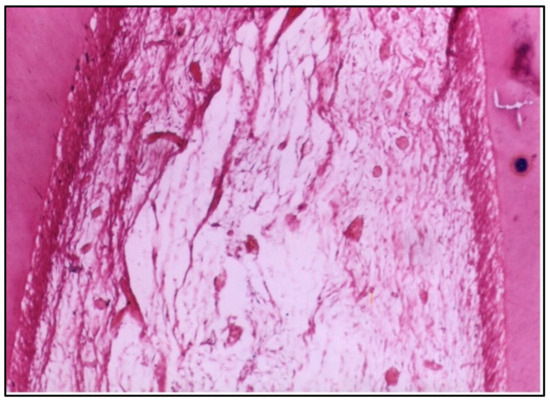

At 2 weeks, the pulp tissue displayed moderate disorganization, but the pattern of damage was more localized compared with Group I. The cells and fibers at one side of the tissue were condensed, which could indicate fibrosis, a common reaction to injury. Meanwhile, the central area was more loosely arranged, reflecting ongoing inflammation (Figure 3). Notably, one of the specimens had a microabscess formation, signifying localized pus accumulation due to infection or significant inflammation, which was more severe than the vascular changes observed in Group I (Figure 4).

Concerning the conventional composite resin, the specimens showed moderate disorganization of the pulp tissue at 2 weeks, with one specimen presenting microabscess formation, indicating localized areas of necrosis and acute inflammation. This aligns with previous studies highlighting the cytotoxic potential of certain composite resins, often attributed to their chemical constituents, such as Bis–GMA and TEGDMA [10].

Figure 3. LS of the pulp (Group II, 2 weeks) showing moderate disorganization of the pulp tissue. Note that the cells and fibers are condensed at one side and loosely arranged in the center (H & E Stain, ×100).